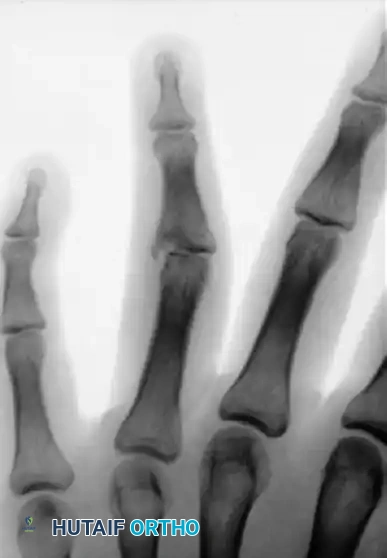

FIGURE 67-72: Malunited fracture of the fifth metacarpal neck treated by open reduction and fixation with one Kirschner wire inserted obliquely. This is rarely necessary because the normal motion of the fifth carpometacarpal joint permits tolerance of up to 40 degrees of angulation at the fracture site.